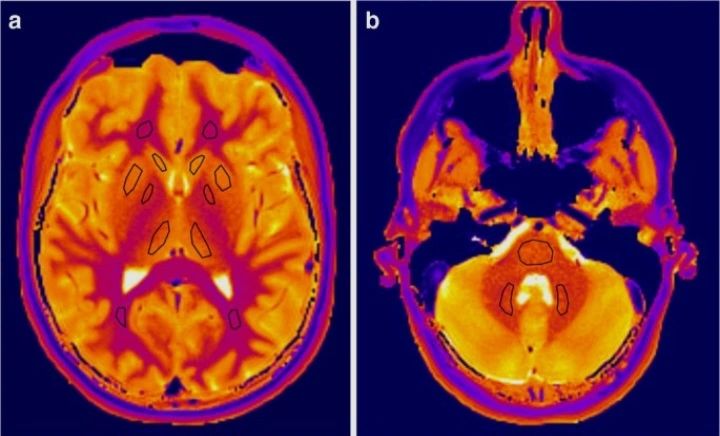

【引言】 今天在海外医学社区看到一份关于脊柱占位活检的病理分享,其展示的形态学陷阱对临床鉴别诊断具有很强的警示意义,搬运供同道参考。 【病史摘要】 患者因颈椎病变伴硬膜外脓肿就诊。外院影像学提示占位性病变,鉴别诊断高度怀疑骨结核(TB)或恶性肿瘤。遂行活检以明确病理。 【被忽视的细节/诊断陷阱】 活检镜下可见旺盛的肉芽组织、慢性炎症背景、显著的上皮样组织细胞增殖以及散在的多核巨细胞,伴反应性成骨。此类表现极易将病理及临床医生的思路引向“肉芽肿性病变(如TB)”或“恶性肿瘤”。 但陷阱在于:在骨与深部软组织中,单纯的骨炎即可引发剧烈的组织细胞聚集和反应性巨细胞增生,这与真正的结构性肉芽肿(Granuloma)有本质区别。本例中并未见典型的干酪样坏死或结构完整的肉芽肿。 【临床启示 (Clinical Pearl)】 【结尾】 骨组织对感染的反应有时极为剧烈,形态学上的“过度解读”可能导致治疗方向的严重偏离。特此分享,仅供临床同道参考。